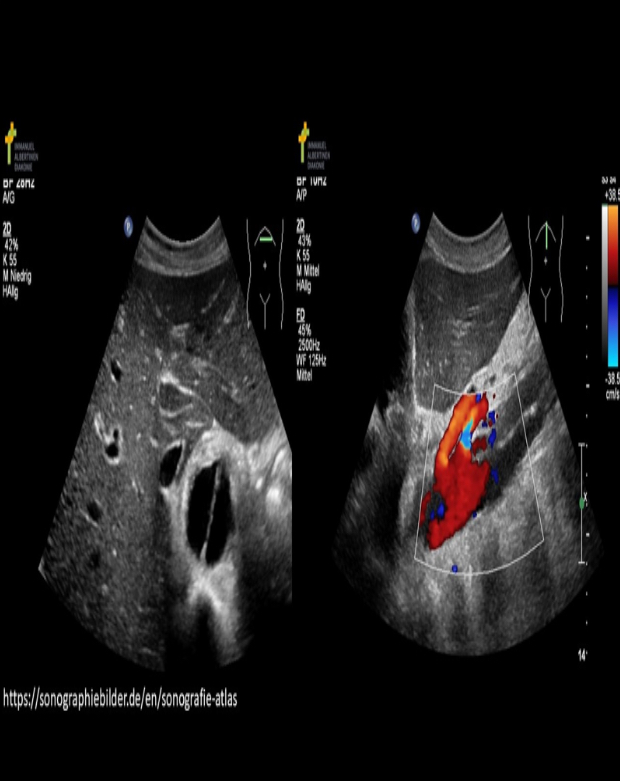

Note the Doppler measurement on the image. What other Doppler measurement should be taken to calculate the resistive index?

A) end diastolic velocity

B) peak systolic velocity

C) end systolic velocity

D) peak diastolic velocity

A) end diastolic velocity B

Why?

The velocities used to calculate the RI are measured by placing the cursor a the true peak systolic velocity and the end diastolic velocity.

RI= PSV-EDV/PSV